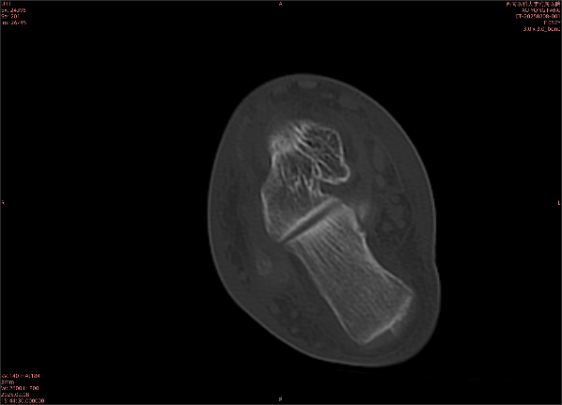

由于無(wú)骨皮質(zhì)中斷,尚不足以引起X線衰減系數(shù)的明顯改變,X線平片無(wú)異常征象;CT在顯示骨皮質(zhì)及軟組織異常方面明顯優(yōu)于傳統(tǒng)X線,特別是三維重建能夠有效的評(píng)價(jià)復(fù)雜骨折,骨外傷CT檢查應(yīng)用廣泛,但CT對(duì)隱性骨折的顯示亦極為有限。

舉例圖像

圖2

專業(yè)解釋看不懂沒(méi)關(guān)系,大家看圖1和圖2就可以了,這是同一個(gè)患者跟骨的磁共振和CT圖像,圖1的紅色箭頭指示的黑線就是磁共振圖像顯示的骨折線,一目了然。而對(duì)比圖2的CT圖像上并未顯示異常。